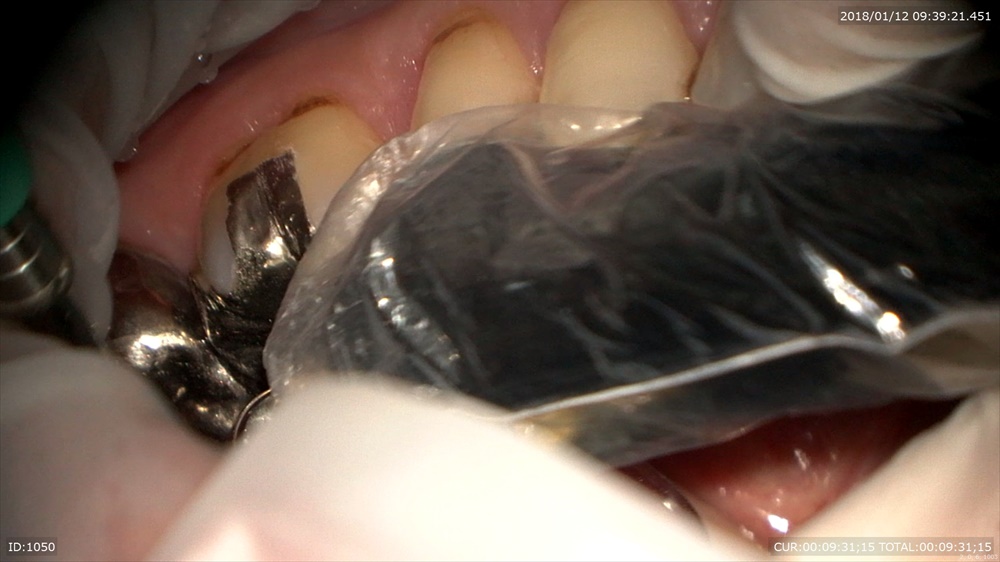

「銀歯むし歯で銀歯がとれた」

一見なにもないように見えて

このセメントの下は。ほらむし歯

感染部位を染めて

マイクロスコープで無痛治療(麻酔していません)

むし歯自体は痛みを感じないのでマイクロスコープで治療を行うとそのような恩恵もあります!

治療中痛みがあるところは知覚があるところ=健康な歯質なのです

丁寧に

次回詰め物がはいります。